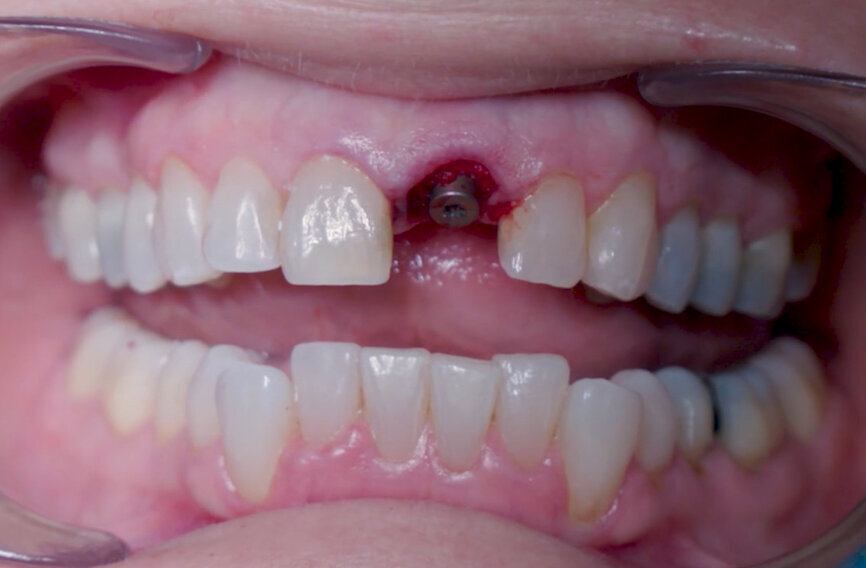

Fig. 12: Final implant position assessment in relation to gingival margins.

Fig. 11: Final implant position assessment.

Fig. 10: Implant placement with surgical handle.

Intra-sulcular incisions were performed to release the marginal gingival fibres to allow a minimally invasive extraction. The socket was carefully cleaned to remove any ligament and debris left. Special attention was given to assessing the alveolar wall integrity. A distance of 3 mm was observed between the gingival margin and the labial wall margin. Implant bed preparation considered a medium-density bone workflow, starting with the needle drill aimed at the palatal wall to create an entry point for the next drills, creating an osteotomy that allows for a greater area of implant engagement (Fig. 5). The Ø 2.2 mm pilot drill was used to the respective implant length planned, followed by the use of an alignment pin to check the 3D orientation (Figs. 6 & 7). The Ø 2.8 mm and Ø 3.2 mm drills were used to finalise the osteotomy (Fig. 8). The site was then properly probed to assess for possible wall perforation. A 4 × 14 mm implant was placed, starting with the surgical handle engaging the apical part of the implant, following the same orientation as that of the needle drill and correcting the implant direction as it moved within the osteotomy (Figs. 9 & 10). Primary stability (45 Ncm) was achieved at the final position. After placement, the implant position was verified horizontally with an occlusal mirror and vertically with a surgical probe, and at this point, the abutment gingival height was selected (Figs. 11 & 12). A healing abutment was placed on to the implant (Fig. 13) to protect the connection so that granular bone substitute (Straumann XenoFlex) could be applied in the gap between the implant and labial wall. This was gently compacted in with the 2.8 mm side of the surgical probe (Figs. 14–16). Collacone (botiss biomaterials) was used to keep the bone granules away from the gingival margins in order to avoid softtissue fenestration and fibroblastic infiltration (Figs. 17 & 18).